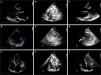

Una mujer de 69 años con miocardiopatía dilatada no isquémica en situación de INTERMACS 3 se le implantó un dispositivo de asistencia ventricular izquierda (DAVI) como terapia de destino al ser rechazada para trasplante cardiaco por niveles de anticuerpos anti-antígenos leucocitarios humanos positivos en alto recuento y comorbilidades. El ecocardiograma prequirúrgico mostró un ventrículo izquierdo gravemente dilatado (diámetro telediastólico de 80mm) sin hipertrofia, septo interventricular de 6mm (figs. 1A-C y vídeo 1 del material adicional). La evolución inicial de la paciente fue satisfactoria, pero a las 24h de la cirugía comenzó con hipotensión refractaria y bajo flujo del DAVI con abundantes eventos de succión, sin respuesta a volumen ni a tratamiento vasoactivo. Se realizó un ecocardiograma donde se observó un ventrículo izquierdo gravemente hipertrófico de forma concéntrica con un septo de 24mm y alta refringencia, sugestivo de edema (asterisco negro, figs. 1D-F y vídeo 2 del material adicional), una imagen de hematoma sobre pared libre de ventrículo derecho (asterisco blanco) y una posición subóptima de la cánula hacia el septo interventricular (flecha blanca). A pesar de la retirada quirúrgica del hematoma, la imagen ecocardiográfica no cambió y continuó su deterioro hemodinámico. Ante la sospecha de que se tratase un edema inducido por la cirugía y el DAVI, se inició tratamiento esteroideo (1.000mg de metilprednisolona/24h/3 dosis). Se consiguió una gran mejoría hemodinámica a las pocas horas y una resolución total del edema 48h después (figs. 1G-I y vídeo 3 del material adicional). La paciente ha sido informada de la publicación de este trabajo y ha firmado el consentimiento para su divulgación científica.